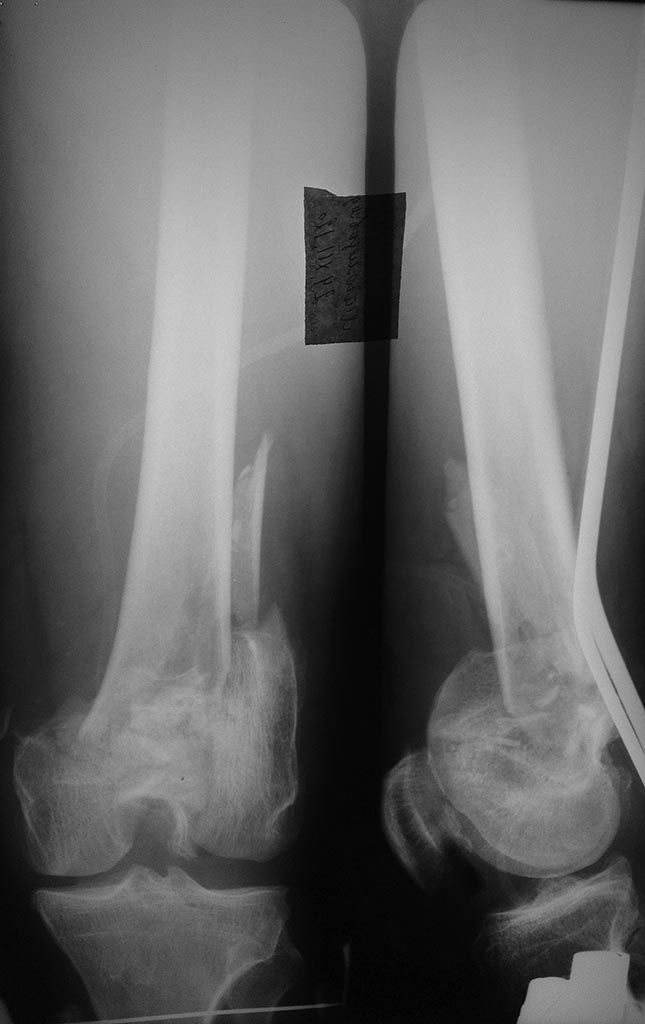

Перелом бедра

пациент мужчина 55 лет травма получена в ДТП 21.12.12г

Перелом очень сложный, я бы не рисковал и LISS. Широка артротомия позволит отрепонировать фрагменты, участвующие в образовании суставной поверхности и зафиксировать их винтами, а потом БИОС ретроградным или универсальным гвоздем.